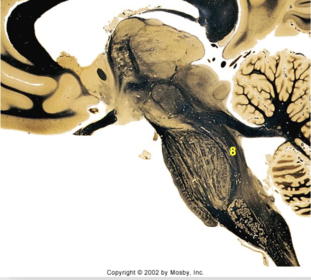

| Head of caudate | |

| Anterior commissure | |

| Thalamus | |

| Substantia nigra | |

| Optic tract | |

| Dentate nucleus | |

| Pons | |

| Longitudinal pontine fibers | |

| Uncus | |

| Superior cerebellar peduncle | |

| Red nucleus | |

| Corticospinal tract (dark) | |

| Pontine nuclei (pale) | |

| Transverse pontine fibers (dark) | |

| Inferior olive | |

| CTT | |

| Medial lemniscus | |

| Nucleus cuneatus | |

| Superior colliculus | |

| Inferior colliculus | |

| Optic nerve | |

| Cerebellum | |

| 4th ventricle | |